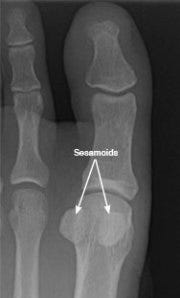

I've been doing a bit of research to figure out the implications of having a sesamoid bone removed. I had never heard of things strange little bones before - how important could they really be??? Turns out, a lot. If you look at the xray below, you may see two pea-shaped bones under each first toe. They look like little floating balls. These are the sesamoids - the inner one is the medial/tibial and the outer one is the lateral/fibular. They are located under the head of the first metatarsal (remember, the big toe joint) and in the tendons of the flexor hallucis brevis muscle.

So what do our friends, the sesamoids, do? Two things:

(1) They absorb impact forces in the foot and help with stability.

(2) They help the big toe move normally and provide leverage when the big toe "pushes off" during walking and running.

Logic says that removing one of these important sesasmoid bones would make the rest of my foot weaker/more susceptible to injury and also cause me to lose stability and push off strength. Hmm.